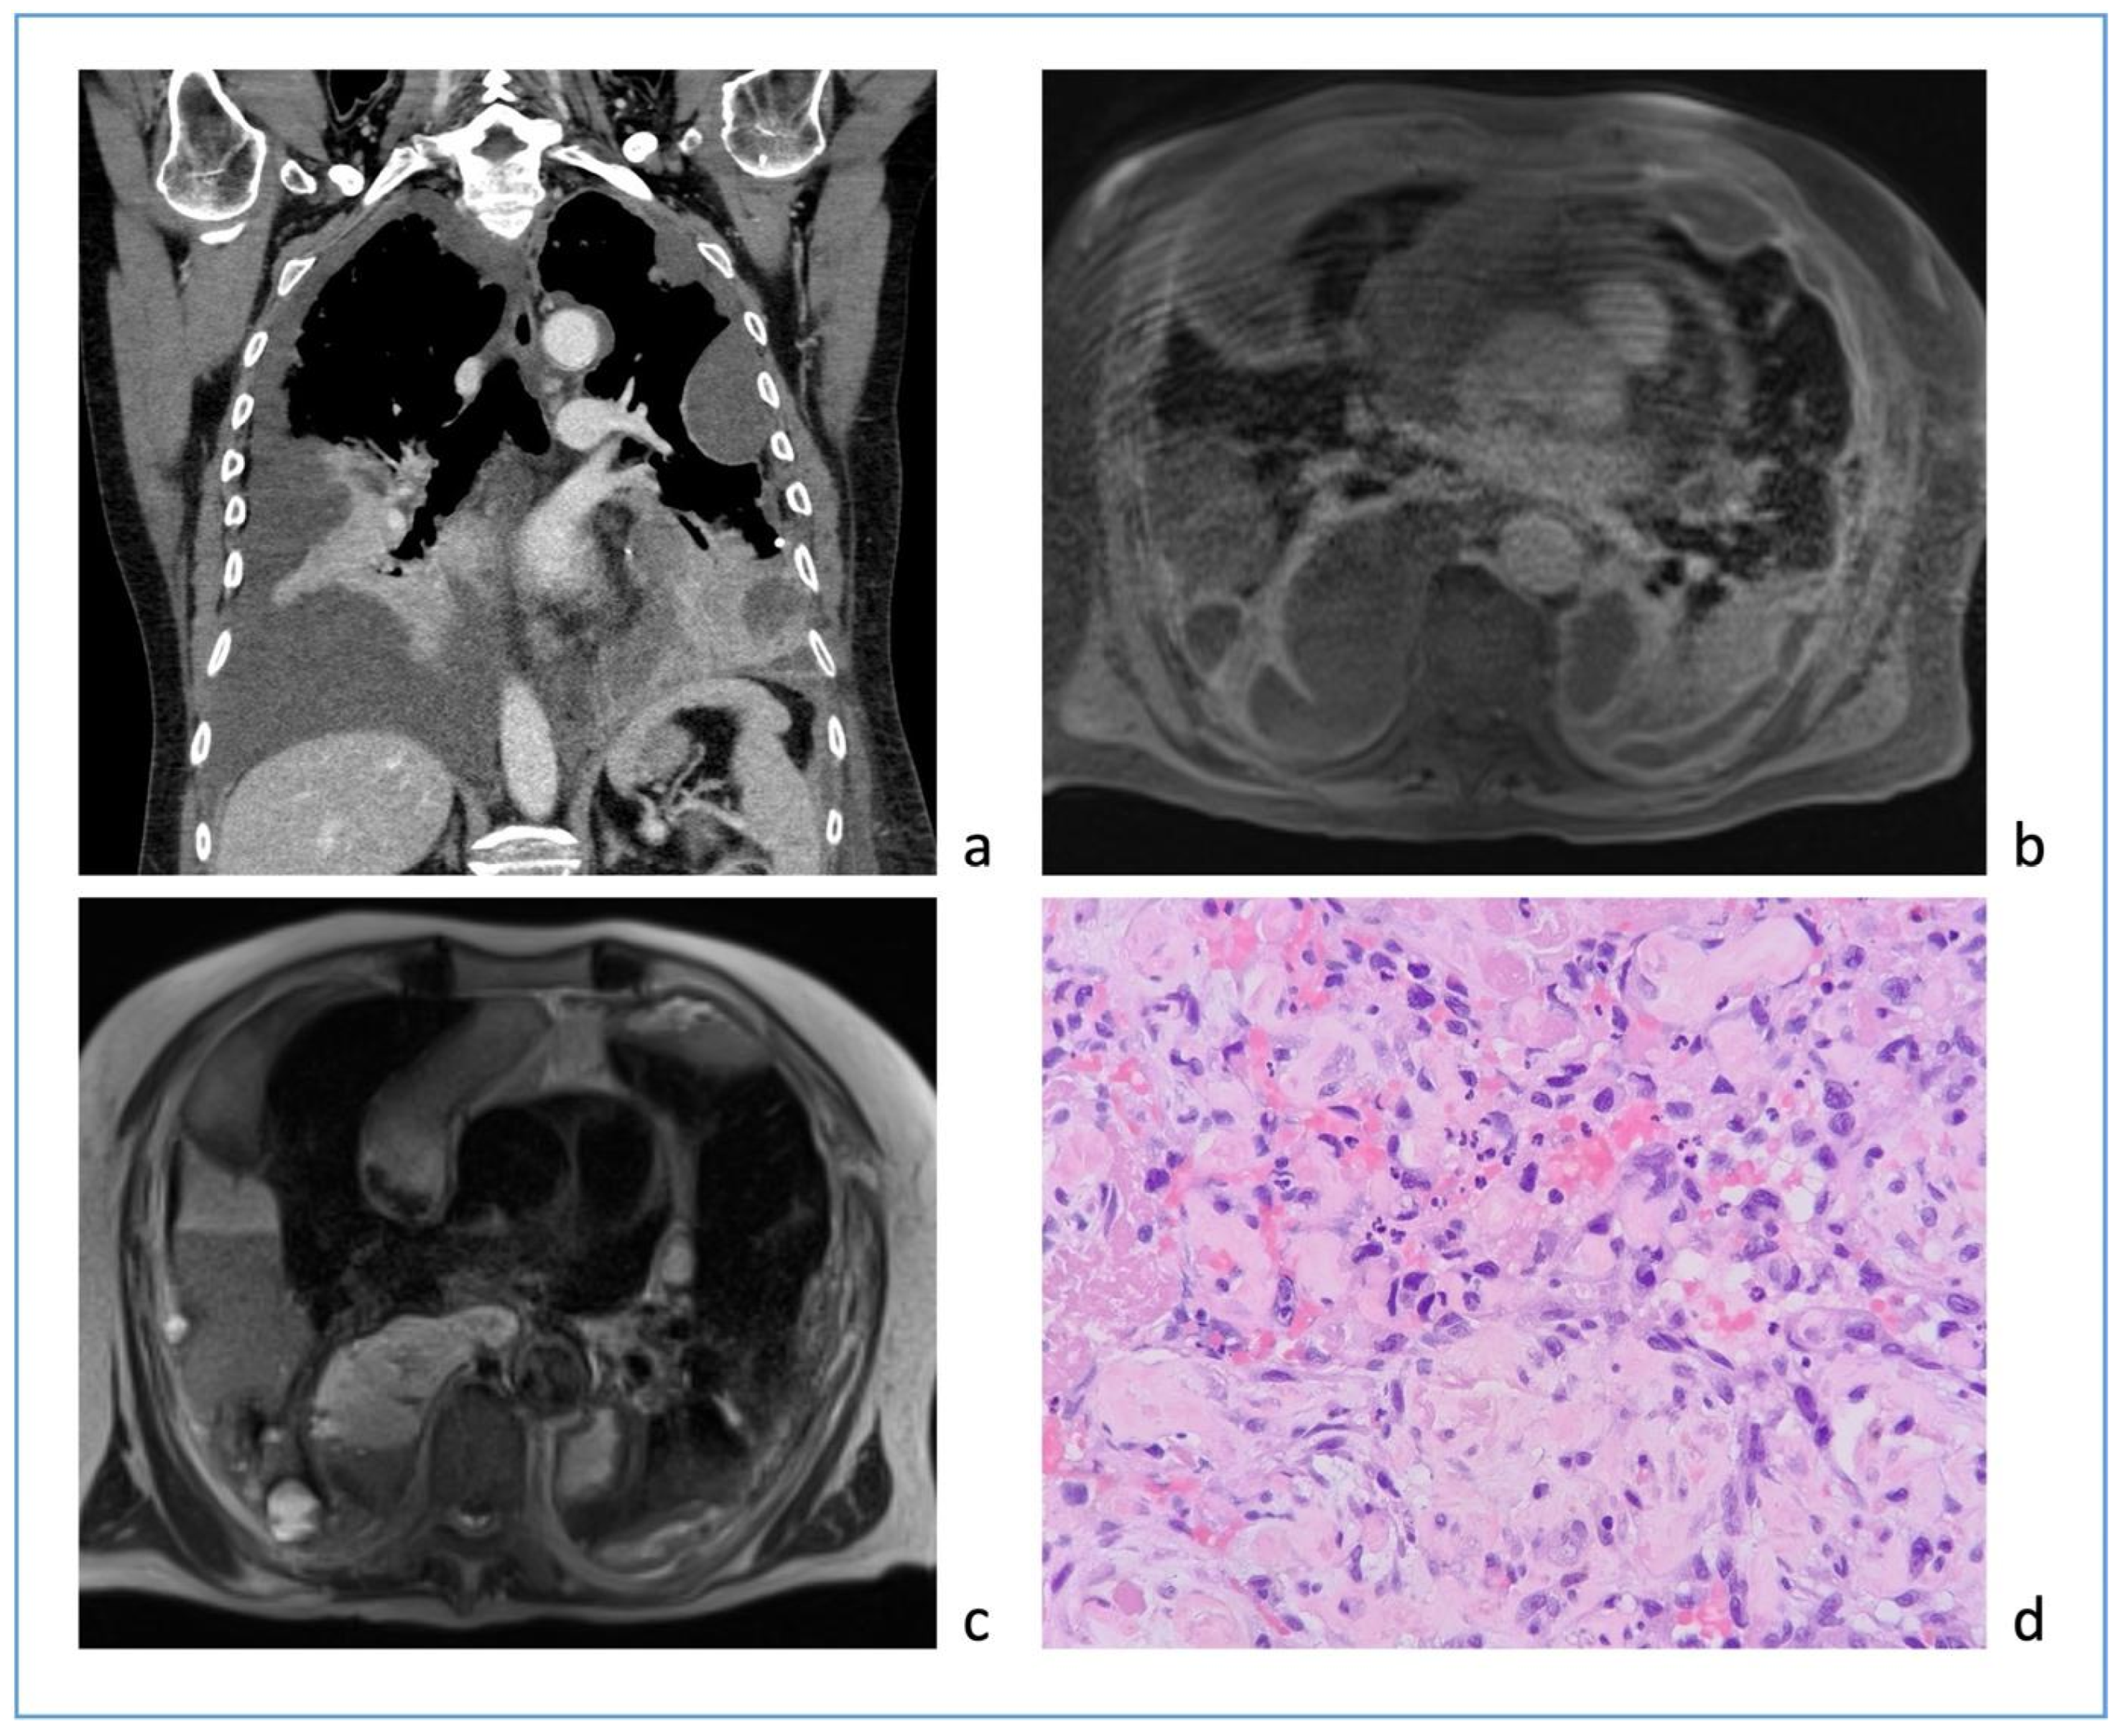

1.7. Abstract 7 (Oral Presentation): Robotic Surgery in Diagnosing Mediastinal Lymphoma Relapses: A Prospective Study

Giacomo Cusumano 1, Rita Aulino 1; Giovanna Motta 2, Francesco Borrata 1, Alessandra Criscione 1, Damiano Calvo 1, Emanuele Fontana 1, Mariapia Gangemi 1, Maurizio Mannino 1, Diomira Tabacco 1, Marco Cavaleri 3, Francesco Di Raimondo 2 and Alberto Terminella 1

• UOC Chirurgia toracica, Azienda ospedaliero universitario Policlinico-San Marco, Catania, Italy

• Unità operativa di Ematologia 1, Azienda ospedaliero universitario Policlinico-San Marco, Catania, Italy

• Servizio di anestesia 1, Azienda ospedaliero universitario Policlinico-San Marco, Catania, Italy

Background: The onset or persistence of anterior mediastinal masses in lymphoma patients undergoing chemotherapy often indicates relapse or persistent disease. Post-chemotherapy thymic hyperplasia can also occur in the same location. CT and FDG-PET scans may be inconclusive for differential diagnosis, necessitating tissue confirmation to avoid overtreatment. The effectiveness of percutaneous or open biopsies depends on the lesion’s location and size, and scar tissue from chemotherapy. Additionally, cytohistological sampling may be inadequate for onco-hematological diagnostics. Robotic surgery is an effective tool for accessing any mediastinal site and is the gold standard in treating mediastinal pathologies. This study explores the use of robotics in invasive diagnostics for persistent or recurrent mediastinal lymphoma, evaluating short-term outcomes, complications, and the ability to obtain representative tissue samples. It compares results with non-invasive techniques like CT and PET, assessing if radiological and metabolic parameters can more reliably predict recurrence or persistent disease rather than thymic hyperplasia or chronic inflammation.

Methodology: This prospective observational study was conducted at the University Hospital of Catania. The analysis focused on patients with a clinical diagnosis of suspected recurrence or persistence of lymphoma with a unique mediastinal location. Data on initial diagnosis and first-line treatment, including clinical and laboratory exams, CT, bone marrow biopsy, and FDG-PET, were collected. All patients underwent a post-treatment FDG-PET scan; those with a positive test were evaluated with a biopsy of the positive lesion. Metabolic response to therapy was assessed using the Deauville criteria. Surgical data, postoperative outcomes, and pathological issues were collected retrospectively. All procedures were performed using the Xi Da Vinci Robotic System (Intuitive, Sunnyvale, CA, USA), guided by PET uptake area.

Results: The study included 20 patients, their clinical characteristics are reported in Table 2. All interventions were performed robotically without the need for conversion and without intraoperative complications. Total thymectomy was performed in 2 cases (10%), while 18 cases (90%) had partial thymectomy. The average postoperative hospital stay was 3.4 ± 0.68 days, with no postoperative mortality or major complications. One patient (5%) experienced a minor complication (wound dehiscence). Pathological analysis revealed relapse in 9 cases (45%). The comparison of PET-derived metabolic parameters and relapse detection showed a significant association with Deauville 5 (Pearson Chi2 12.7; p-value < 0.001). An increase in the SUV max/hepatic mean SUV ratio also showed a significant correlation (p-value = 0.003).

Conclusions: This study confirms the importance of surgical histological typing and suggests robotic surgery as a promising technique for diagnosing lymphoma relapses, with significant benefits in safety and diagnostic accuracy. Deauville score 5 and the SUV max/hepatic mean SUV ratio are reliable predictors of relapse. The study emphasizes the importance of histological confirmation in the presence of suspicious PET uptakes.